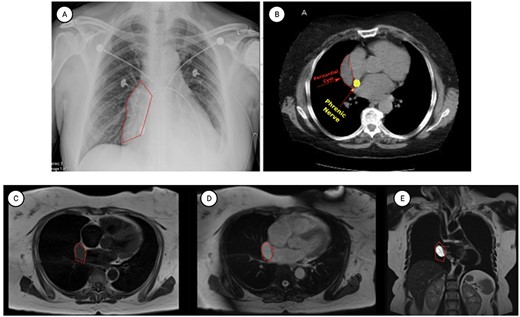

At the time of presentation to the pulmonologist, the patient was afebrile with a normal cardiopulmonary exam and vital signs. Chest X-ray revealed an enlarged right-sided heart border (Fig. 1). CT showed multiple sub-centimeter bilateral pulmonary nodules as well as a 6 x 2 cm right-sided pericardial cyst (Fig. 1). Further evaluation by MRI demonstrated gadolinium enhancement on T2 sequences with hypo enhancement noted on T1 sequences, confirming that the lesion was fluid-filled and cystic in nature.

Representative images of pericardial cysts on commonly employed imaging modalities. (A) The chest X-ray imaging of the patient described in the case report AP CXR showing widened mediastinum in a patient with a wide differential diagnosis which ultimately was found to be pericardial cyst. (B) CT imaging of the patient described in the case report with representative images of our patient demonstrating a sizeable pericardial cyst marked with red arrows and its close association with right phrenic nerve marked in gold. (C–E) MRI T1 (C) and T2 (D–E) appearances of pericardial cysts. Representative images of pericardial cyst appearance on gadolinium-enhanced MRI sequences. *Figure edited with BioRender.